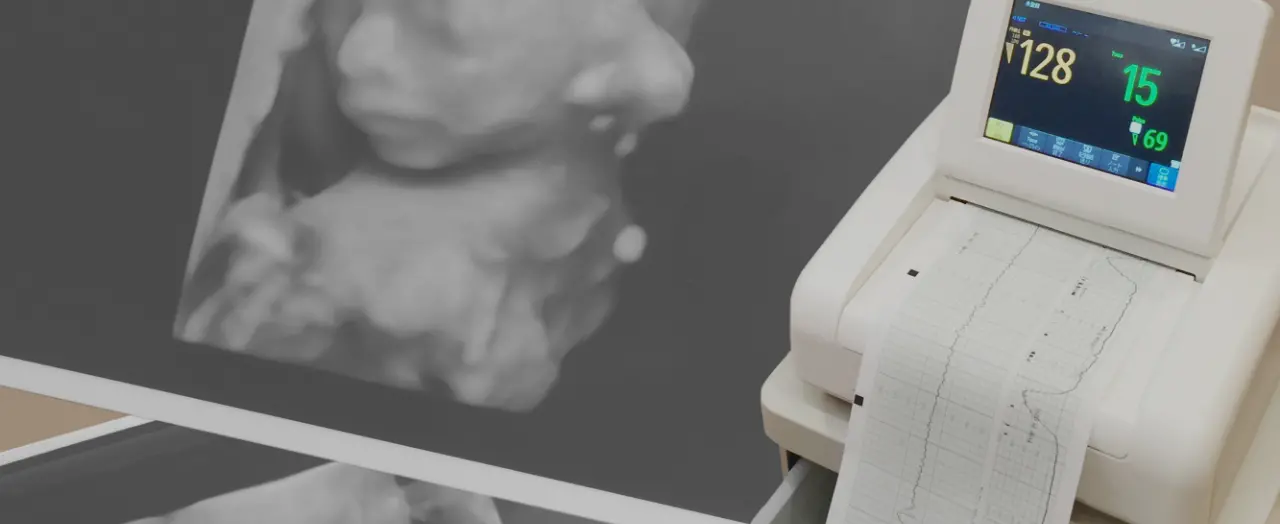

最近では、妊娠中の定期健診でも4D超音波画像で赤ちゃんの様子がとてもよく見えるようになりました。赤ちゃん研究においても、先進的な機器の使用や研究者の努力によっておなかの中の赤ちゃんのことが色々とわかってきています。

妊娠5~6週目ぐらいから、赤ちゃんの動きを確認できているようで、成長していくとおなかの中で「指しゃぶり」をしたりすることが確認されています。羊水を飲み込んだり、吐き出したり、あくびをしたり、しゃっくりをしたり、これらの動きを「呼吸様運動」といい、ママの羊水から生まれ出たら、すぐに自分で呼吸をするためのものと考えられています。また、おしっこをしたり、ハイハイのような足の動きも練習しているようです。